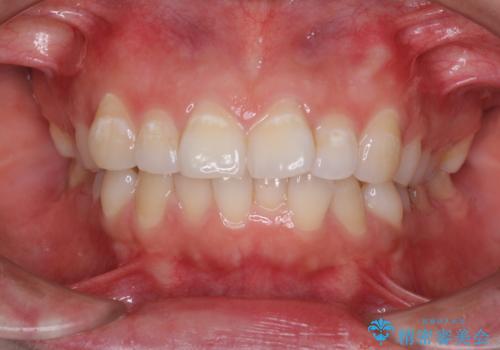

前歯の出っ歯と口の閉じにくさを抜歯矯正で改善 目立たないワイヤー矯正

担当医 藤巻太一朗